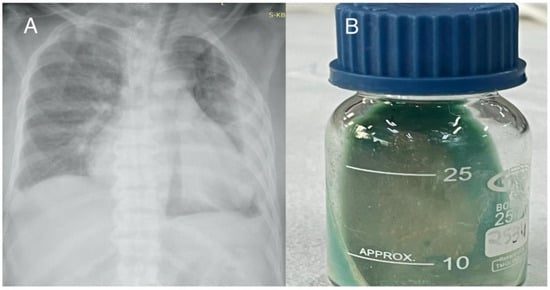

Case 3

Case 4